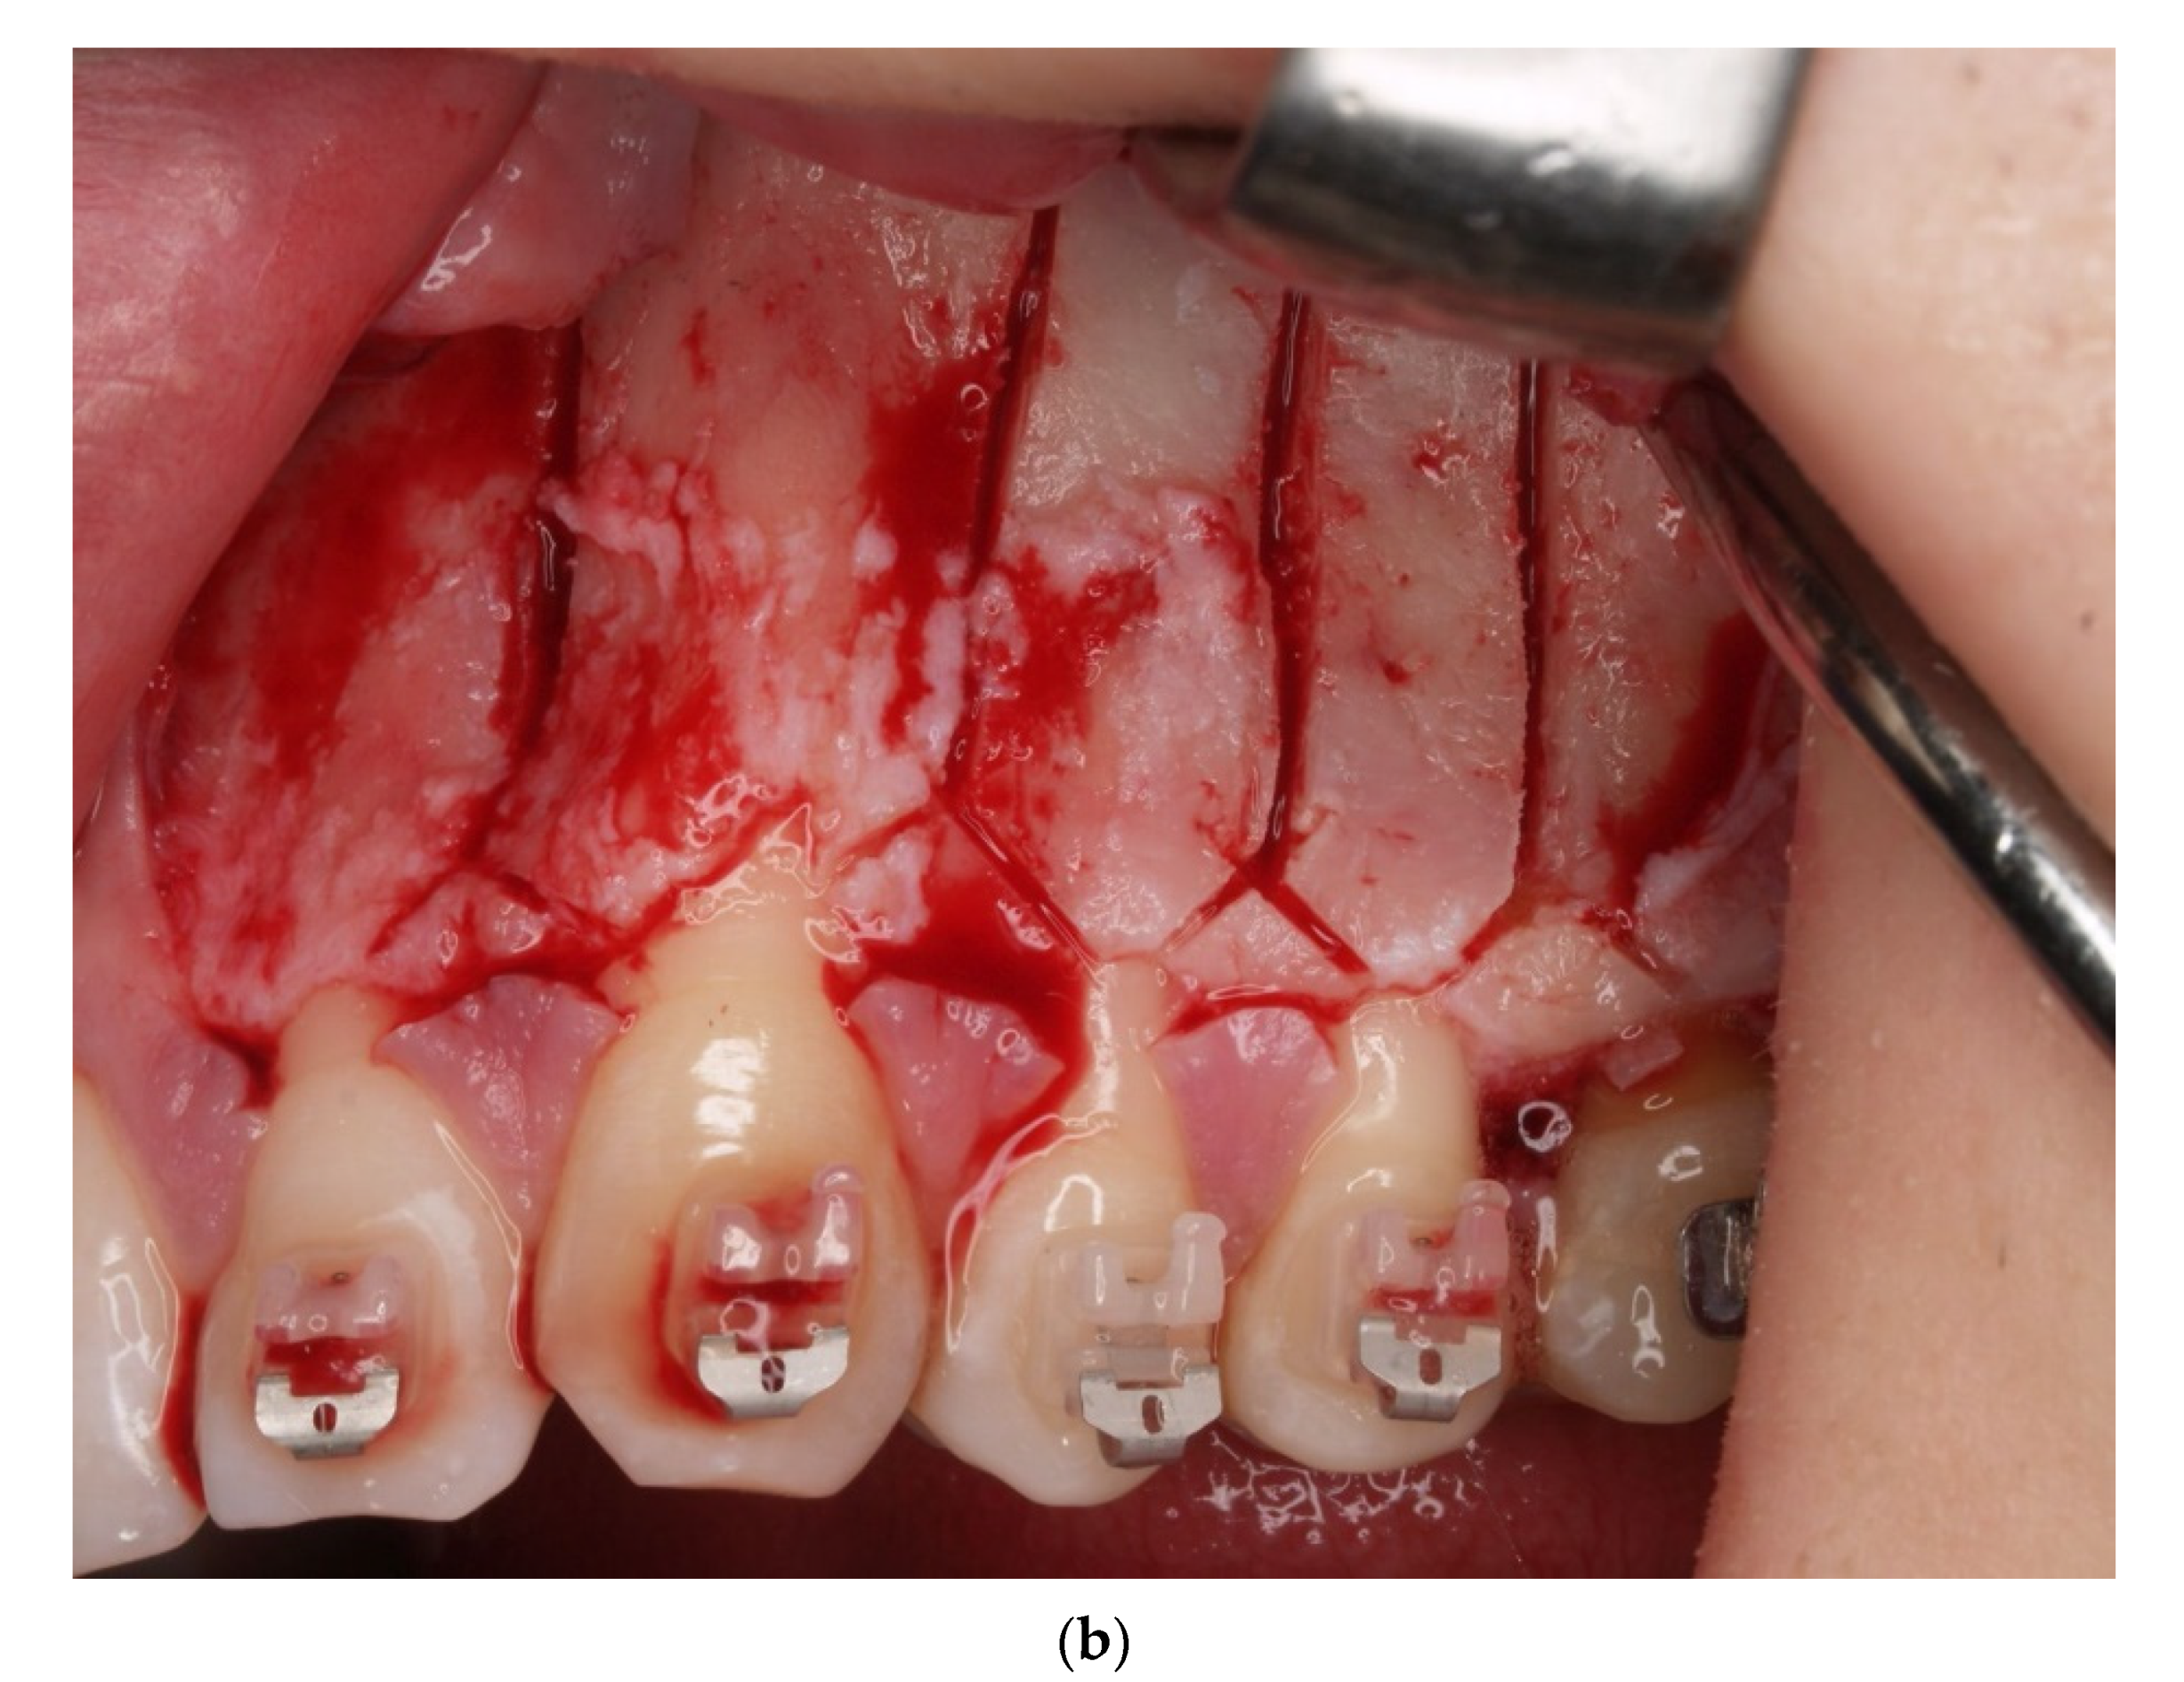

2. Materials and Methods

4. Results

- Sulewska, M.; Duraj, E.; Bugała- Musiatowicz, B.; Waszkiewicz -Sewastianik, E.; Milewski, R.; Pietruski, J.; Sajewicz, E.; Pietruska, M. Assesment of the effect of the corticotomy-Assisted orthodontic treatment on the maxillary periodontal tissue in patients with malocclusions with transverse maxillary deficiency: A case series. BMC Oral Health 2018, 18, 162. [Google Scholar] [CrossRef]